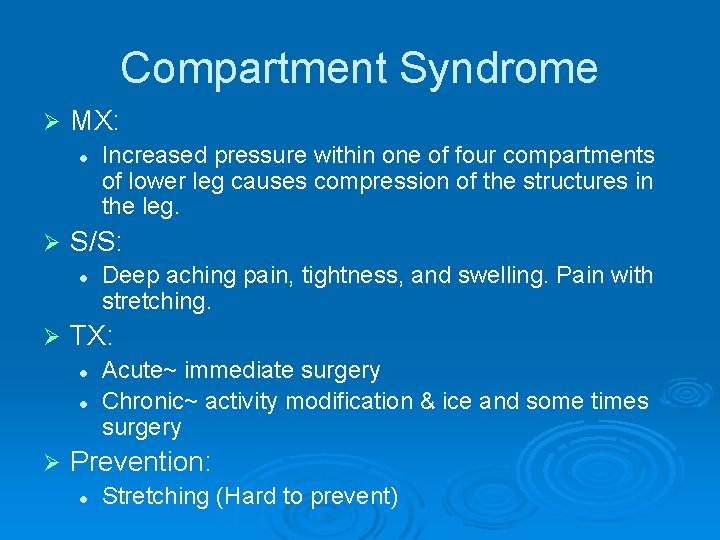

Compartment Syndrome Ø MX: l Ø S/S: l Ø Deep aching pain, tightness, and swelling. Pain with stretching. TX: l l Ø Increased pressure within one of four compartments of lower leg causes compression of the structures in the leg. Acute~ immediate surgery Chronic~ activity modification & ice and some times surgery Prevention: l Stretching (Hard to prevent)